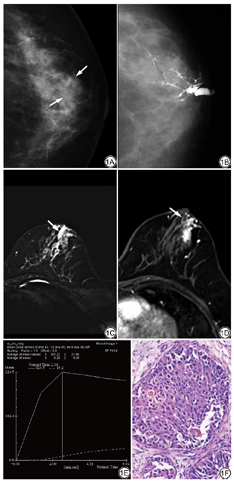

45例48个患乳GL的影像表现如下:(1)导管扩张40个,多发生在主导管,其次为二级导管,少见三、四级导管,表现为不同程度、不均匀性增宽;(2)导管僵直呈枯树枝状13个;(3)导管边缘毛糙、模糊8个;(4)导管破坏4个(1个为乳头状瘤伴硬化性腺病,3个为DCIS伴微浸润);(5)导管扭曲5个;(6)导管细小2个(1个末端局部稍增宽,然后狭窄呈鼠尾状,为乳腺增生,另一个导管细小,但有中断,为IDC);(7)正常1个(导管乳头状增生);(8)对比剂进入间质2个(1个为导管乳头状瘤,另1个呈潭湖征,为IDC);(9)有1个显示导管外有一肿块,该导管呈受压征象,术后该肿块为导管乳头状瘤,说明该肿瘤发生在另一支导管内;(10)充盈缺损33个;(11)多发结节状囊状充盈区7个,有4个于囊内见充盈缺损;(12)导管中断20个,其中在导管中断处和该导管支配区域见多发微钙化2个(均为恶性病变,图1),中断区见肿块2个(1个为恶性,1个为导管乳头状瘤伴重度不典型增生)。

45例48个患乳MRI表现如下:(1)导管显示43个,可扩张或不扩张,表现为自乳头向后的管状影,T1WI及T2WI可为高、低、等信号,信号高低与溢液性质有关,往往T1WI及T2WI信号相反,有4个信号相同,于T1WI及T2WI均呈高信号,其中2个为血性溢液,应与出血距检查时间的长短有关;7个恶性病变均见管状异常信号,这些管状信号往往与导管分布一致,可是连续的、间断的或突然中断(图1);(2)肿块样强化(22个,有2个为囊实性病变,肿块最大为31 mm×42 mm×24 mm,为囊实性肿块,病理为导管乳头状瘤)、灶点强化(7个)、非肿块样强化(7个)、导管样强化(9个)、环状或串环状强化(4个),这些强化灶可是单一的、多发的或混合的强化,多在病变导管支配范围内或中断处;未见强化(6个);(3)对41个病变测量了ADC(有6个因未见强化灶和1个强化灶小而无法测量),16个<1.150×10-3 mm2/s(其中包括5个恶性病变);(4)EER:15个<80%,26个>80%,7个恶性病变3个<80%,4个>80%(同样有6个因病变未见强化和1个病灶小无法测量);(5)TIC:Ⅰ型23个、Ⅱ型6个、Ⅲ型13个,未见强化6个(分别为导管乳头状瘤1个、乳腺增生伴囊肿1个、导管上皮乳头状增生1个、乳腺增生3个),7个恶性病变Ⅰ型1个、Ⅱ型4个、Ⅲ型2个;(6)MIP图显示血运增加13个,正常35个,7个恶性病变血运增加6个,正常1个。

GL BI-RADS分类及MRI BI-RADS分类与病理结果对照见表1。本研究把病理结果为乳腺癌、导管乳头状瘤、不典型增生的病例定为阳性发现(因为外周型导管乳头状瘤、不典型增生为癌前病变[20],是值得关注的病变,而中央型导管乳头状瘤,虽然通常不会恶变,但也是需临床干预的病变,即使穿刺结果为大导管乳头状瘤,也需要进一步切取活检[4]),把其他定为阴性。根据表2及表3,GL及MRI对PND诊断的敏感度、特异度、阳性预测值、阴性预测值、准确度之间差异均无统计学意义(P>0.05)。把GL及MRI评价为BI-RADS 4~5类的病变定为阳性发现,其他定为阴性表现(表4),GL与MRI对有乳头溢液的乳腺癌的敏感度、阴性预测值均为100.00%,且准确度一致;仅把BI-RADS 5类的病变定为阳性发现时(表5),MRI对有乳头溢液的乳腺癌的敏感度(85.71%)明显高于GL(42.85%),二者均有很高的特异度及准确度。